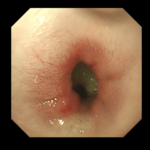

- 診断方法:X線および内視鏡検査

- 処置:内視鏡ガイドでストマックチューブを用いて慎重に胃内に落とし込む。

- 経過:摘出後は嘔吐や食欲不振もなく、順調に回復。軽度の炎症あり。

- 内視鏡処置の利点としては外科的な開腹手術等を回避でき、組織へのダメージがありません。